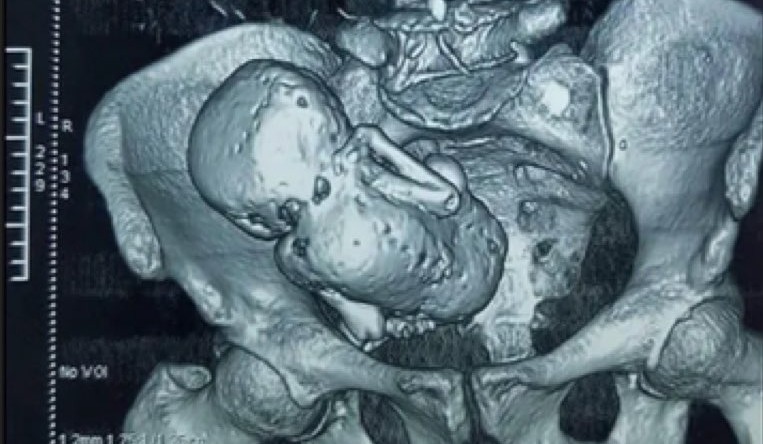

باغی ٹی وی: چین کی ایک خاتون ہوانگ ییجون نے 92 سال کی عمر میں بچے کو جنم دیا، مگر جب ڈاکٹروں نے ان کے بچے کو دیکھا تو ان کے ہوش اڑ گئے، کیونکہ ان کا بچہ پتھر بن چکا تھا،دراصل ہوانگ 1948 میں 31 سال کی عمر میں ماں بننے والی تھیں، مگر کچھ ایسا ہوا کہ انہیں اپنا بچہ 61 سال تک پیٹ میں رکھنا پڑاجب انہیں پتہ چلا کہ وہ ماں بننے والی ہیں تب انہیں خوشی توکافی ہوئی،مگر جب ڈاکٹروں نے بتایا کہ ان کی ایکٹوپک پریگنینسی ہے تو وہ فکر مند ہوگئی تھیں۔

ہوانگ کے معاملے میں بچہ زندہ نہیں بچا ان کے پیٹ میں پرورش پا رہا بچہ اتنا بڑا ہوگیا تھا کہ اس کا جسم خود بخود باہر نہیں نکل سکتا تھا ڈاکٹروں نے اس سے نجات کیلئے سرجری کرانے کا مشورہ دیا تھا، کیونکہ اس کو رکھنے سے بعد میں صحت سے وابستہ پریشانیاں لاحق ہوسکتی تھیں لیکن سرجری کی لاگت خاتون اور اس کے اہل خانہ کیلئے کافی زیادہ تھی ہوانگ نے آپریشن کو نظر انداز کرنے کا فیصلہ کیا۔

ایک ڈاکٹر نے این بی سی نیوز کو بتایا کہ جب ایسے معاملات میں بچہ اتنا بڑا ہوجاتا ہے کہ جسم قدرتی طور پر اسے باہر نہیں نکال پاتا تو مردہ بافتوں کے پاس کیلشیم جمع ہوجاتا ہے۔ اس تبدیلی کے نتیجہ میں ایک ’اسٹون بے بی‘ بنتا ہے۔ جو خواتین اس کا تجربہ کرتی ہیں وہ اکثر اس سے انجان رہتی ہیں۔

آخر کار 2009 میں 92 سال کی عمر میں انہوں نے 60 سال سے رحم مادر میں موجود جنین کو ہٹانے کیلئے سرجری کروائی اور جب بچہ باہر نکلا تو اسے دیکھ کر ڈاکٹرز بھی حیران رہ گئے، کیونکہ وہ مکنمل طور پر پتھر بن چکا تھا۔